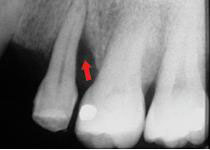

治療前牙周有垂直骨缺損

治療後6個月牙周骨再生